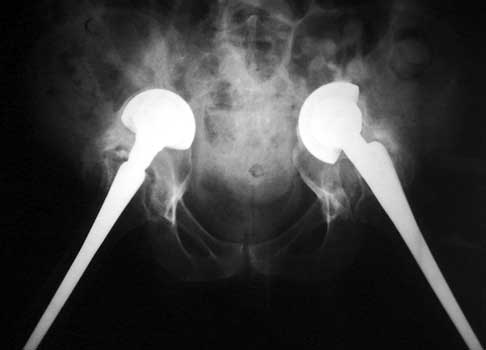

Very abnormal positioned cup. No comparison radiographs were available. Current radiographs demonstrates markedly tilted cup which has migrated laterally from pelvis.